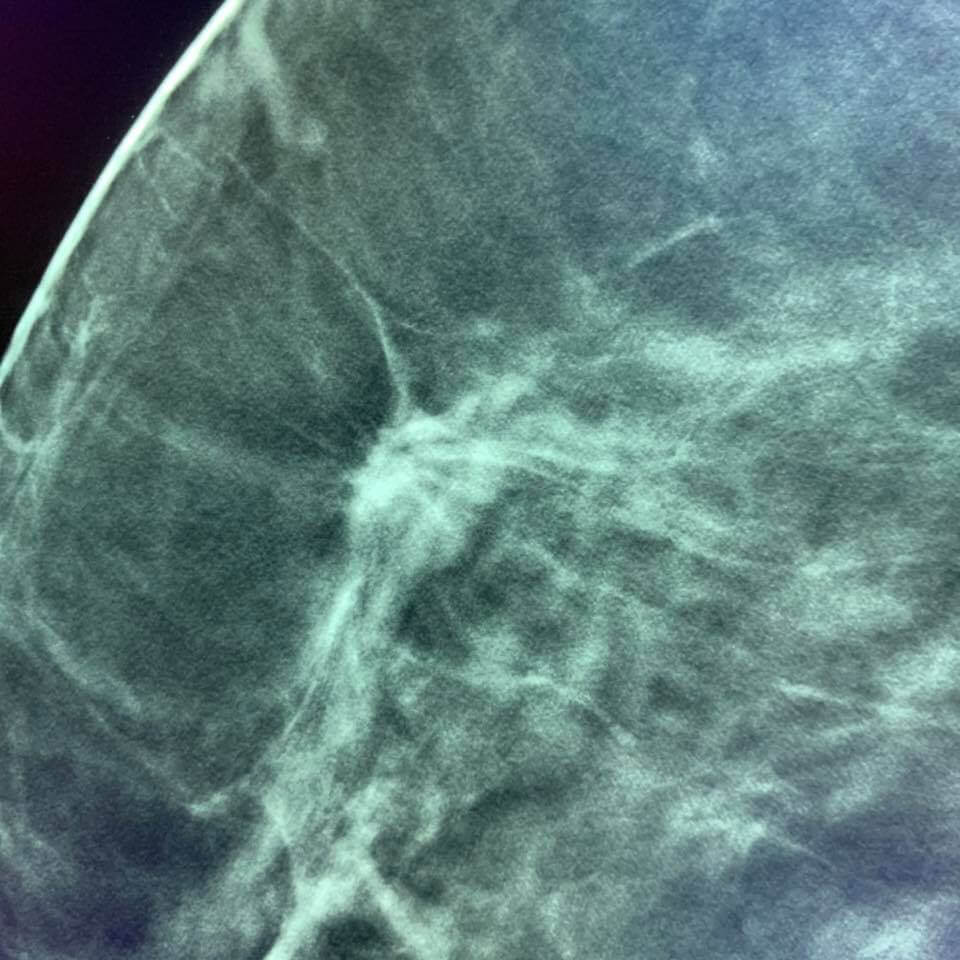

Une femme de 73 ans, mammographie de dépistage. Deux ans avant, sa mammographie de dépistage était considérée comme normale par deux lecteurs.

À première vue, la nouvelle mammographie mammaire a également été considérée comme normale et inchangée par rapport à la précédente, mais MammoScreen a mis en évidence une lésion sur le sein droit.

L’analyse rétrospective de la précédente par MammoScreen a montré la même zone.

L’IRM a mis en évidence une masse spiculée sur le sein droit.

Finalement, un autre radiologiste a réussi à la localiser grâce à l’échographie et a effectué une biopsie guidée par l’échographie. La biopsie confirme un carcinome mammaire invasif de type luminal A.